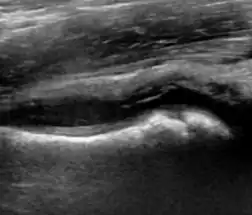

During childhood, ultrasound is a quick method to assess hip pain and quite often may be used to avoid use of irradiating techniques, such as radiography or CT. Ultrasound allows evaluation of joint effusion, synovial thickening and neovascularity, the bone/cartilage contour, and the femoral head-neck alignment. Although sonography is extremely sensitive in detecting increased synovial fluid, it is nonspecific and cannot be used with accuracy to determine the type of fluid. Transient synovitis of the hip, despite being the most frequent cause of pain in children between 3 and 10 years, remains a diagnosis of exclusion. It usually shows anechoic fluid, but echogenic fluid can also be found. The effusion is considered pathologic when it is measured at >2 mm in thickness. The differential diagnosis is wide, including osteomyelitis, septic arthritis, primary or metastatic lesions, LCPD, and SCFE. Discrimination from septic arthritis is challenging, often requiring joint aspiration. In septic arthritis, US is able to demonstrate a hip joint effusion, synovial thickening, and cartilage damage, although the appearances are nonspecific.[1]

A step between the head and the physis can be detected in children with SCFE, while abnormalities in the femoral head contour may suggest the presence of LCPD. In both cases, radiographs are mandatory to confirm diagnosis and severity (Figure 12).[1]

Figure 12: